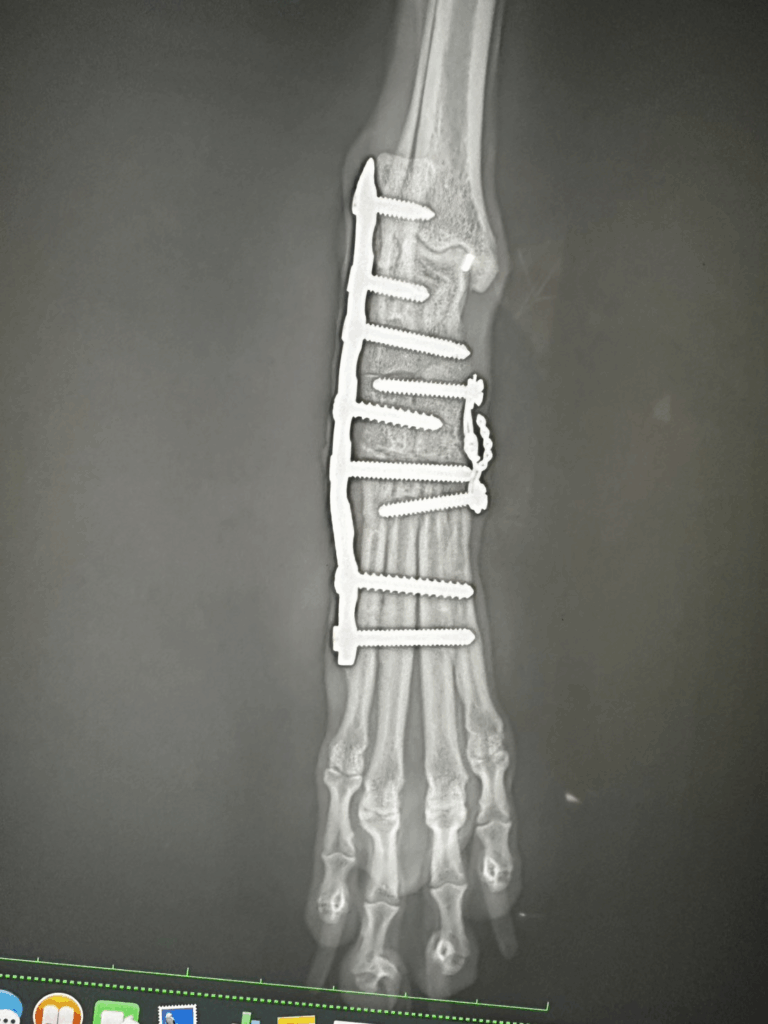

- 手術による整復と固定

- ピンやスクリューを用いた骨の安定化

- 手術後のリハビリ・再建トレーニング

特に重度の場合は、放置すると関節が変形して歩行困難になることもあるため、

早期の整形外科的治療が非常に重要です。